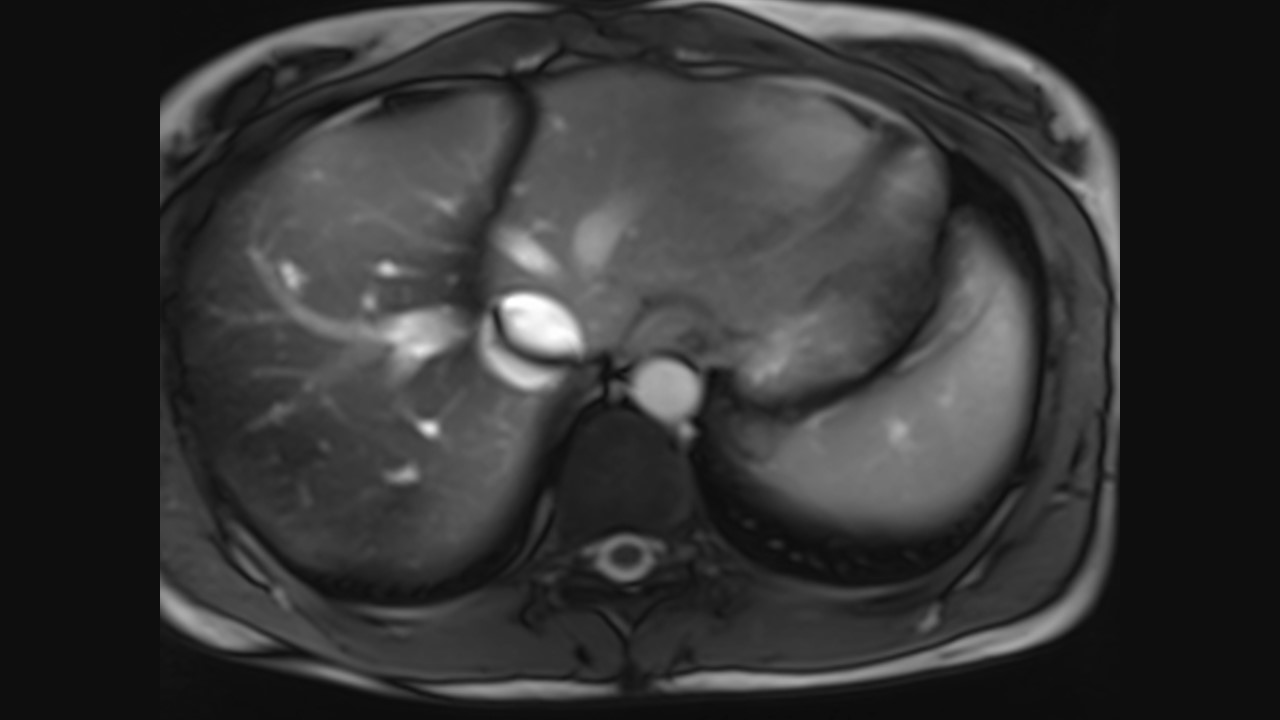

Axial Series